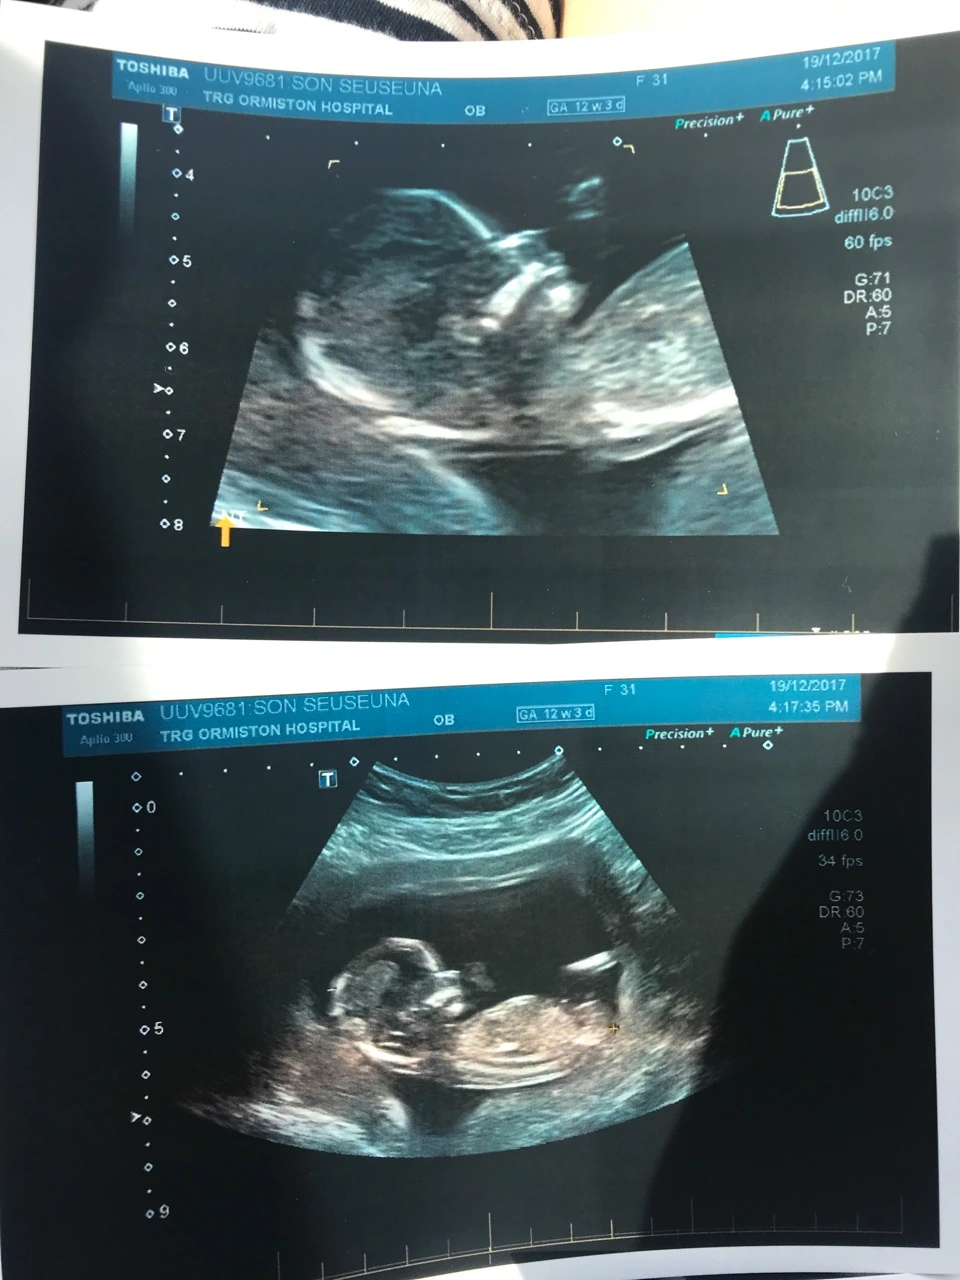

아기 엘림이의 사람다운 첫 초음파 사진. 2017년 12월 19일, 임신 12주 3일차. (4개월)

뉴질랜드에서 12주 차 임산부는 두 번째 초음파를 찍게 됩니다. 이날은 특별히 NT Scan이라 불리는 목 투명대 검사를 집중적으로 하게 되는데요, 태아 목둘레 검사란 태아 목 뒷부분의 피부 아래 투명대의 두께를 측정하는 검사로 임신 11~13주 6일 사이에 초음파를 통해 측정할 수 있습니다. 모든 아기들의 투명대 속에 액체가 들어있는데 다운증후군 아기의 경우 이 액체의 양이 더 많습니다.

태아 목둘레 검사는 다운증후군 위험도를 측정하는 선별검사입니다. 선별검사를 통해 다운증후군 위험도를 가늠한 후 고위험군으로 판단될 경우 융모막 융모검사(CVS)나 양수천자 검사와 같은 진단 검사를 통해 보다 정확한 진단을 내릴 수 있습니다. 이러한 진단 검사의 경우 확률이 아주 낮긴 하지만 검사 자체로 인한 유산의 위험이 있다는 단점이 있습니다.

그럼에도 불구하고 태아 목둘레 검사만으로 아기의 다운증후군 여부를 확실하게 가려낼 수는 없기 때문에 진단검사를 시행해야만 정확한 진단을 내리는 데 도움이 될 수 있습니다.

엘림이의 목 투명대 두께는 안전 범위였고 초음파를 봐주던 전문가는 "모든 게 정상이야. (All is normal.)"라고 말했습니다. Normal이라는 단어가 이렇게 기분 좋게 들리기는 처음이었습니다. 보통인 경우, 평범한 경우에 자주 썼던 Normal 이 이렇게 기분 좋은 단어였을 줄이야. 앞으로의 임신기간 동안 모든 엘림이의 상황과 저의 상황이 Normal이기를.. 하나님 앞에 기도드렸습니다.